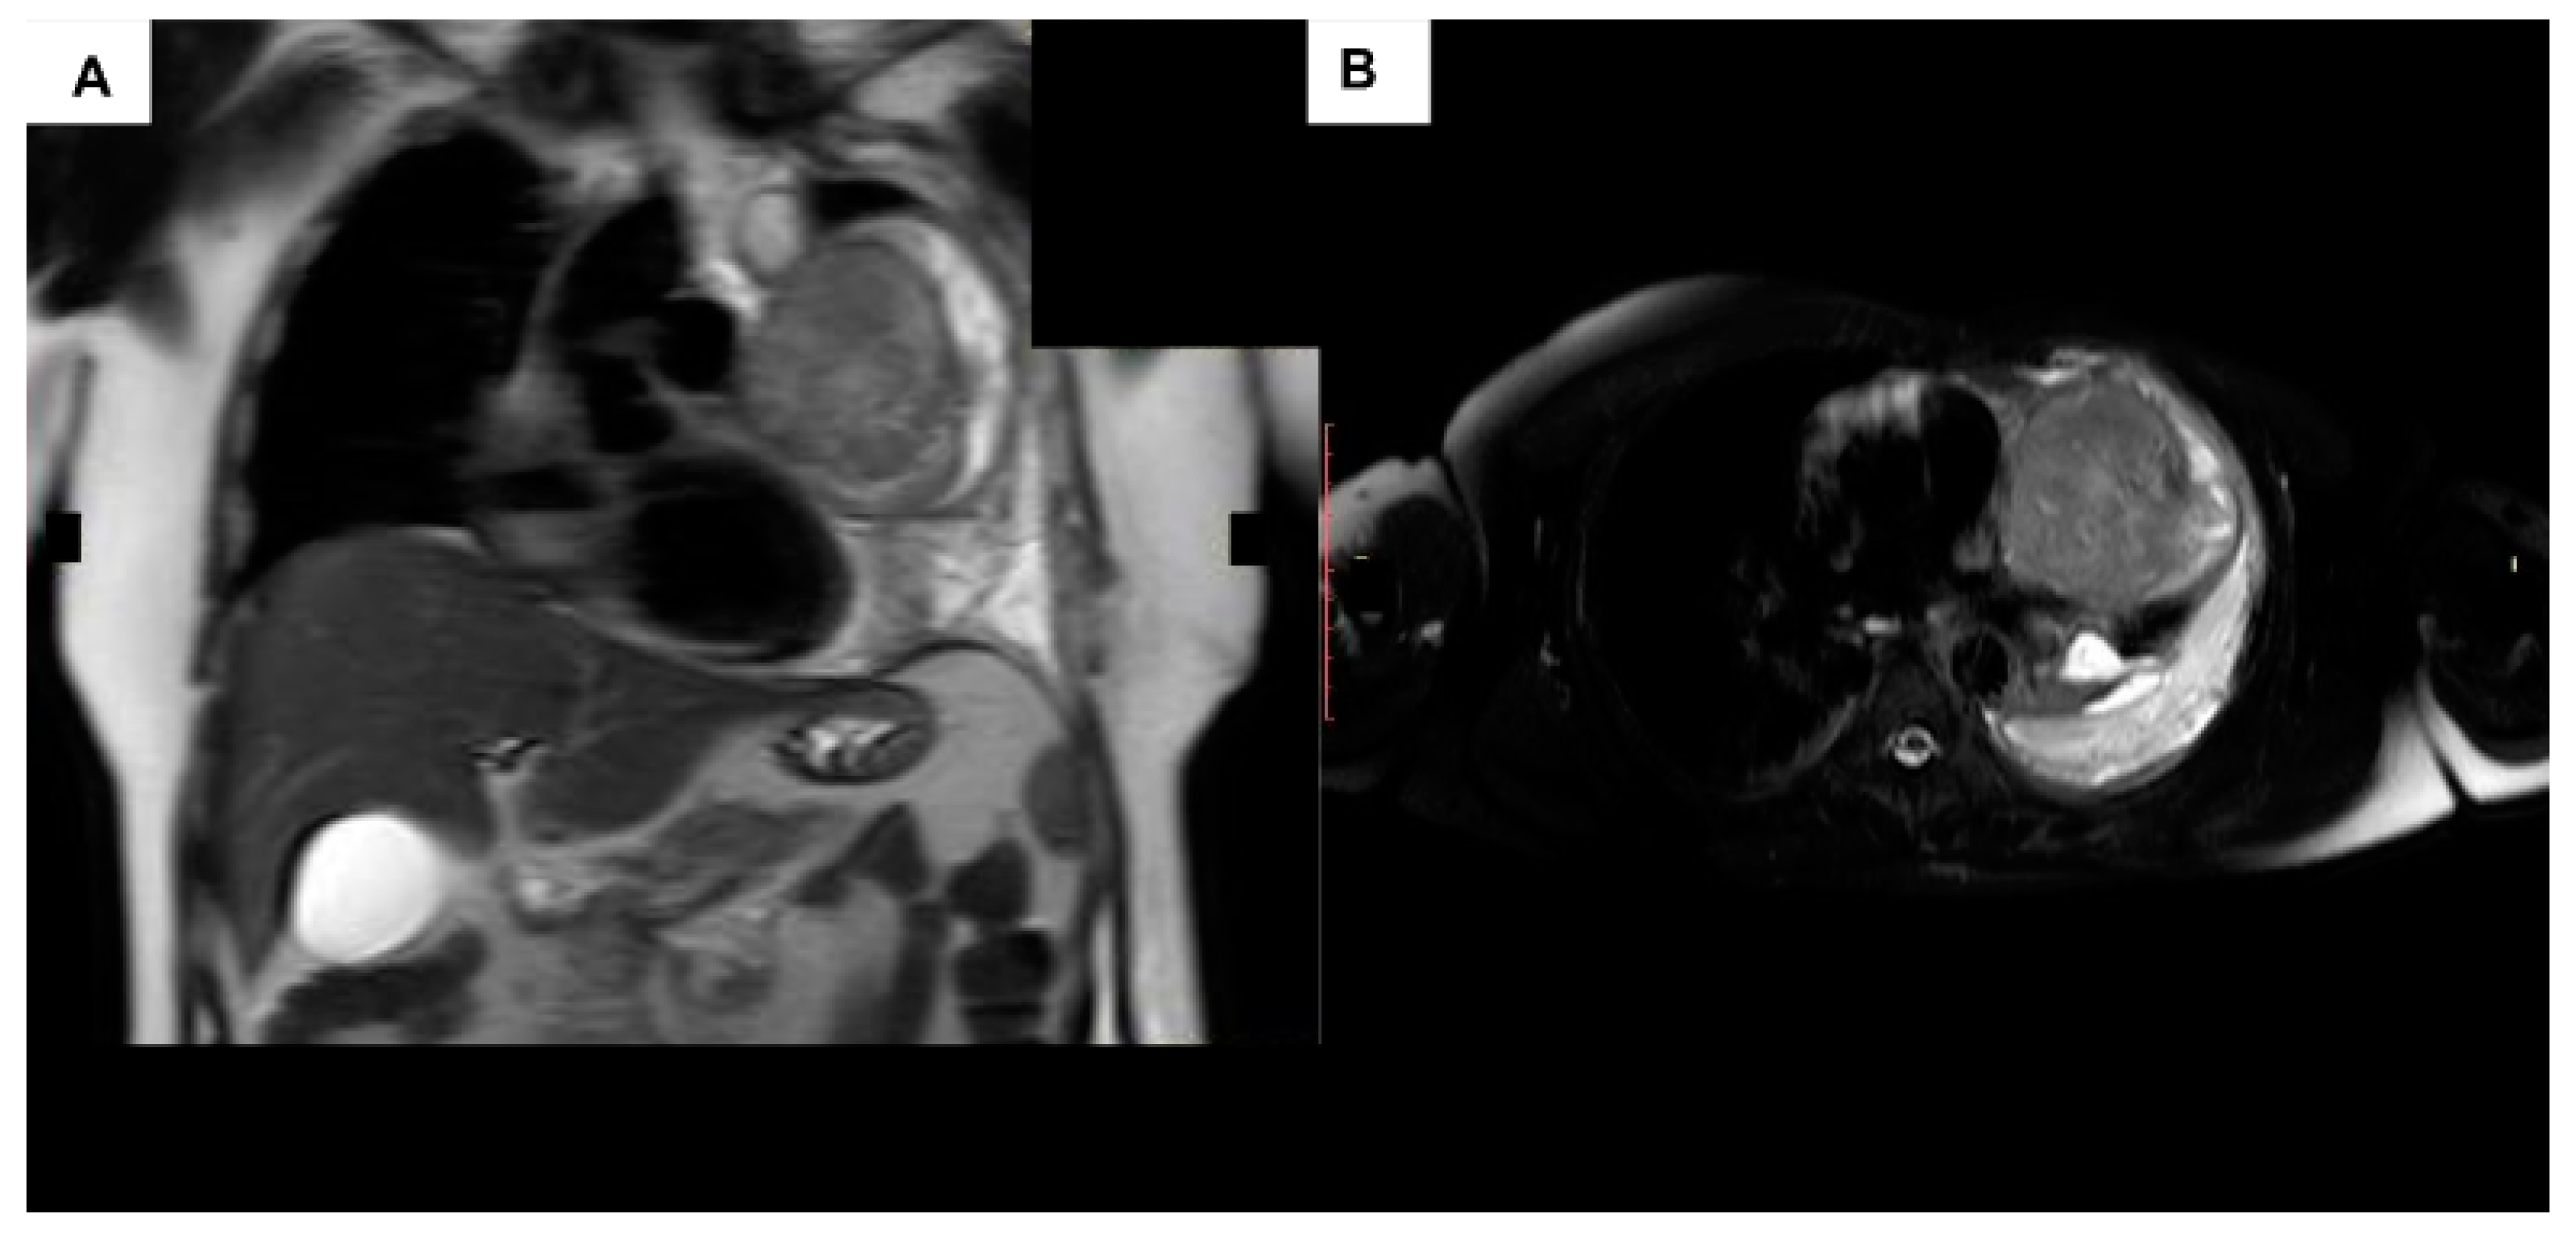

- Chaudhry, I.U.; Rahhal, M.; Khurshid, I.; Mutairi, H. Radical surgical resection for giant primary mediastinal endodermal sinus tumour with pulmonary metastasis after chemotherapy: Can be curative. BMJ Case Rep. 2014, 2014, bcr2014204662. [Google Scholar] [CrossRef]

- Zhu, F.; Wang, L.; Zhai, X. Primary mediastinal yolk sac tumor: A case report and literature review. Int. J. Clin. Exp. Pathol. 2020, 13, 2772–2777. [Google Scholar] [PubMed]

- Tanase, B.; Burlacu, A.; Mugescu, M.; Neicu, A.; Radoi, S.; Constantinoiu, S.; Horvat, T. Malignant Extramucosal Esophageal Tumor—Yolk Sac Tumor—Case Report. Chirurgia 2022, 117, 222–229. [Google Scholar] [CrossRef]